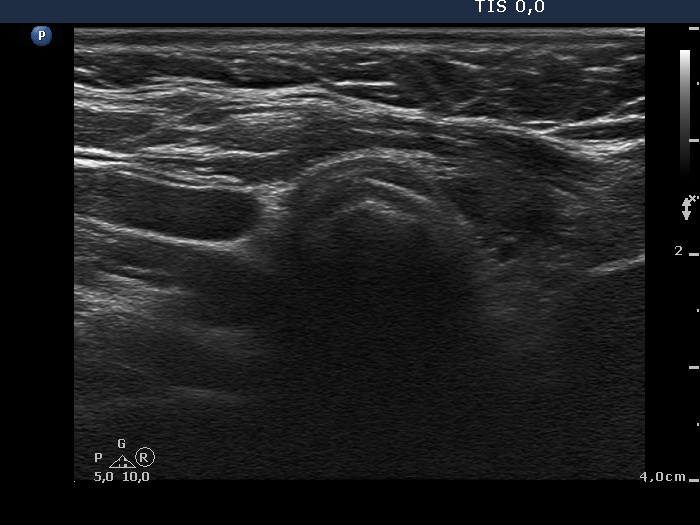

Ultrasonography: There was no parenchyma according to the right lobe, while there was a relatively large thyroid tissue in the left lobe. The latter displayed increased vascularization.

Ultrasonography: The pattern remained unchanged.